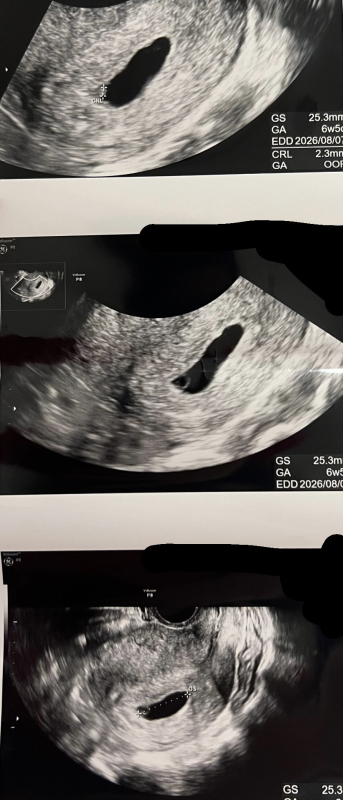

最終月経開始日が10/15で現在9w1dayなのですが病院に行き、妊婦検診を受けました。一個前の検診の際は6w6dayの時で、胎嚢が確認できていました。今回病院に行き、胎嚢は前より大きくなっており、卵黄嚢もできていると言われたのですが、赤ちゃんの姿が確認できておらず、心拍の確認ができていない状態です。次の妊婦検診が丁度1週間後の来週になり、そこで心拍が確認できなかったら稽留流産の確率が高いと言われました。病院の先生によると時期が早いのかもしれないとのことでしたが、不安な気持ちでいっぱいです。妊娠していることを気にせず、食事やパートナーと性行為はしていたのですがそれがだめだったのでしょうか。なんでもいいので教えていただきたいです。

エコーで胎嚢は大きくなっていたものの、心拍が確認できずご心配になりましたね。実際にエコーを拝見しているわけではないので、はっきりしたことは明言できませんが、まずは週数経過とともに胎嚢が大きくなってきているようですので、お子さんなりにしっかりと発育はなさっているのではないかと思いますよ。

妊娠9週

お写真の掲載もありがとうございます。今は経過を見ていくしかない時期で、もどかしいですよね。ですが、あまりご心配なさらずに、暖かくしてゆったりとお過ごしくださいね。